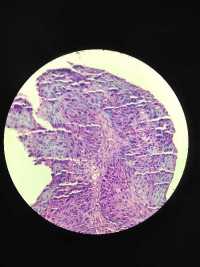

最近一段时间活检组织,染色苍白,尤其是胃肠食管,肿瘤细胞都白的不能看,请教一下这是什么原因,别的都可以,就活检的不行,排除了脱水及脱蜡

图1

图2

图3

图4

和伊红有没有关系,我用的是醇溶性的

用水溶性的试试